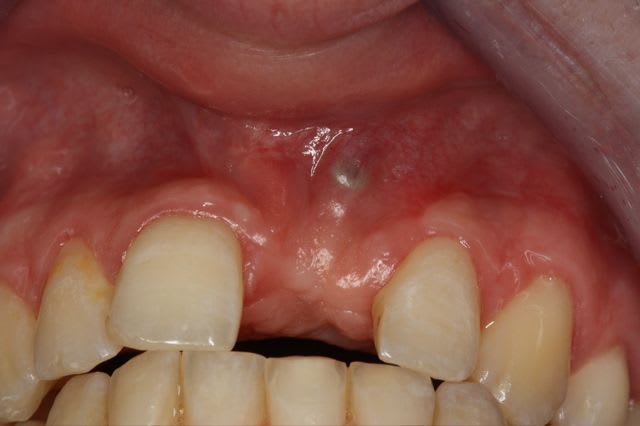

dépose des vis et pose de l'implant à 5mois1/2 avec un cj roulé et mise en place de la vis de cica,

et 3 mois 1/2 après empreinte

15j après essayage pilier et biscuit, visite au labo pour "finition en bouche" et 3 h après scellement.

le liseré visible en cervicale n'est pas le pilier mais le petit suintement dut à la sonde pour enlever les excès de ciment